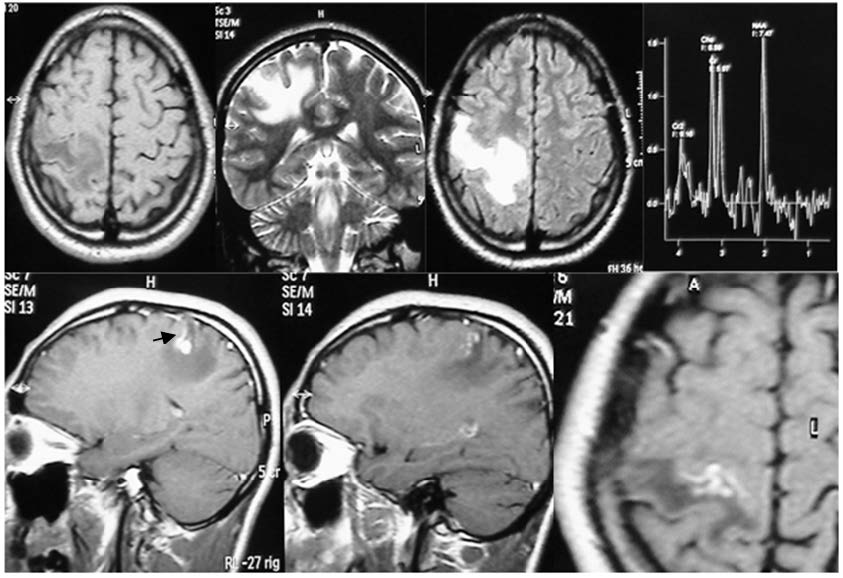

Acompañamos la presente comunicación con imágenes de RM en las que se grafica el «vaso centinela» a nivel frontal derecho (figura 1), fronto-parietal derecho (figura 2) y fronto-temporal derecho (figura 3).

Imágenes de RM sin gadolinio: corte axial en T1 y FLAIR, y corte coronal en T2. RM con gadolinio: cortes sagital y axial. Se observa un granuloma fronto-parietal derecho con aspecto similar al anterior, un edema vasogénico y la flecha señala a un vaso captador. Una secuencia de espectroscopía muestra la leve elevación del pico de la colina